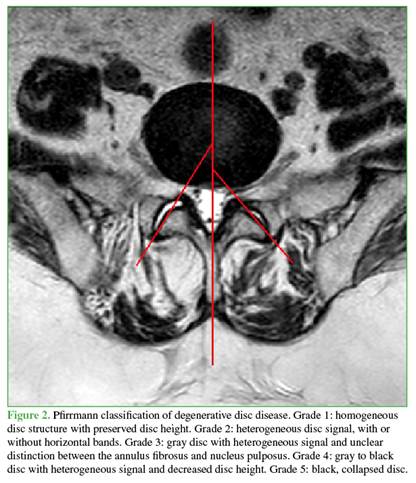

Magnetic resonance imaging studies were evaluated using a Siemens Espree 1.5 Tesla high field scanner. A total of 300 lumbar levels at L4 to L5 and L5 to S1 were analyzed in 150 patients, including 87 women and 63 men, with an age range from 33 to 82 years. Bilateral facet joint inclination angles were measured, as illustrated in Figure 1, along with the difference between facet inclinations on both sides and the degree of disc degeneration according to the Pfirrmann classification9 shown in Figure 2.

Based on disc degeneration severity, patients were divided into two groups. Mild degenerative disc disease included Pfirrmann grades 1, 2, and 3, whereas severe degenerative disc disease included grades 4 and 5. Facet tropism was considered present when there was a difference of 5 degrees or more between the inclination of the facet joints on each side.1,10 Facet angles were measured on the mid axial slice of the corresponding disc, parallel to the inferior endplate of the superior vertebral body.

In contrast to studies reporting a significant correlation between facet tropism and degenerative disc disease, our study did not demonstrate an association between facet tropism and severe degenerative disc disease. This discrepancy may be partially explained by differences in how disc degeneration was classified. In the present study, degenerative disc disease was divided into mild and severe categories based on Pfirrmann grades, whereas other studies considered only the presence or absence of degeneration, or used different grading groupings.2,9,12-15 Özdemir and Boyalı found no statistically significant relationship between facet tropism and degenerative disc disease at the L3 to L4, L4 to L5, and L5 to S1 levels.13 Noren et al. also reported no association between the magnitude of facet tropism and the presence of degenerative disc disease at the same lumbar levels.3 Vanharanta et al. found no significant correlation between the presence of facet tropism and degenerative disc disease, nor between the magnitude of the facet tropism angle and disc degeneration.16 These findings are consistent with those of our study. Similarly, Boden et al. and Kong et al. reported no association between facet tropism and degenerative disc disease.17,18 In contrast, Gao et al. reported that facet tropism was associated with three degenerative conditions related to disc disease: degenerative spondylolisthesis, degenerative scoliosis, and lumbar disc herniation.14 Karatas et al. reported a significant association between facet tropism and degenerative disc disease at L5 to S1, while Pichaisak et al. observed a similar association at L4 to L5.4,19